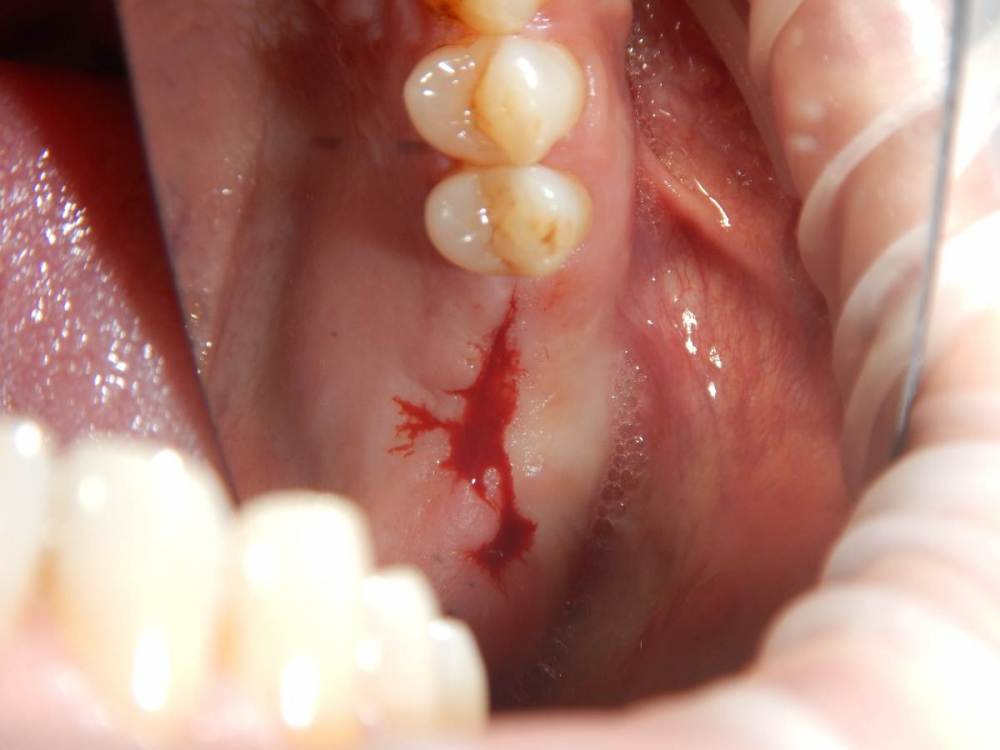

annda Опубликовано 11 июня, 2021 Поделиться Опубликовано 11 июня, 2021 (изменено) Ничего не беспокоит.Зубы удалены лет 15 назад Изменено 11 июня, 2021 пользователем annda 1 Ссылка на комментарий

Карен Аванесов Опубликовано 11 июня, 2021 Поделиться Опубликовано 11 июня, 2021 Анна здравствуйте. Версий много, вскрытие покажет, главное нет признаков воспаление, в любом случае интересный клинический случай под минимальное вмешательство, обязательно покажите развязку. 1 Ссылка на комментарий

Astronaft Опубликовано 11 июня, 2021 Поделиться Опубликовано 11 июня, 2021 Радиография была один в один с вашим случаем. Результат биопсии: рецидуальная киста с кристаллами холестерина. Но конечно может быть что-нибудь другое. 4 Ссылка на комментарий

annda Опубликовано 12 июня, 2021 Автор Поделиться Опубликовано 12 июня, 2021 (изменено) Спасибо всем. Вмешательства не было, кроме удаления. Я так понимаю, тактика заключается в доступе и банально кюретаже? Графт по убеждениям, дефект все одно получается практически четырехстеночный... Главное, не наджабить кортикалку ГП. Я так понимаю, процесс все же из пазухи, был с зубами связан? Изменено 12 июня, 2021 пользователем annda Ссылка на комментарий

Astronaft Опубликовано 12 июня, 2021 Поделиться Опубликовано 12 июня, 2021 (изменено) В моем случае процесс одонтогенный. Киста это остаток после удаления зуба. В вашем случае не должен быть из пазухи. Да - там есть истончение кортикальной пластины в одном месте, но вроде как без инвагинации. Границы везде четкие, т.е. процесс доброкачественный. Из пазухи в кость можно проникнуть только инвазивно. Лизис, а не раздвигание. Карцинома - границы были бы другие. Т.е. процесс либо происходит из самой кости, или одонтогенный. Изменено 12 июня, 2021 пользователем Astronaft 1 Ссылка на комментарий